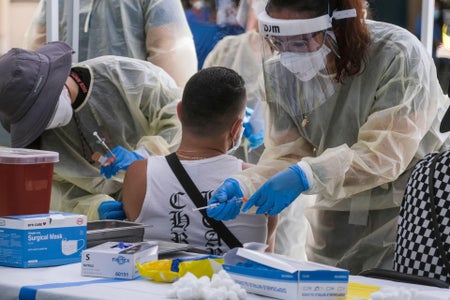

Monkeypox Is a Sexually Transmitted Infection, and Knowing That Can Help Protect People

In the U.S., Black and Latino men who have sex with men are most vulnerable to monkeypox

U.S. Monkeypox Response Has Been Woefully Inadequate, Experts Say

Testing bottlenecks and vaccine rollout problems have let the monkeypox virus spread unchecked, echoing the mistakes of the U.S. COVID response